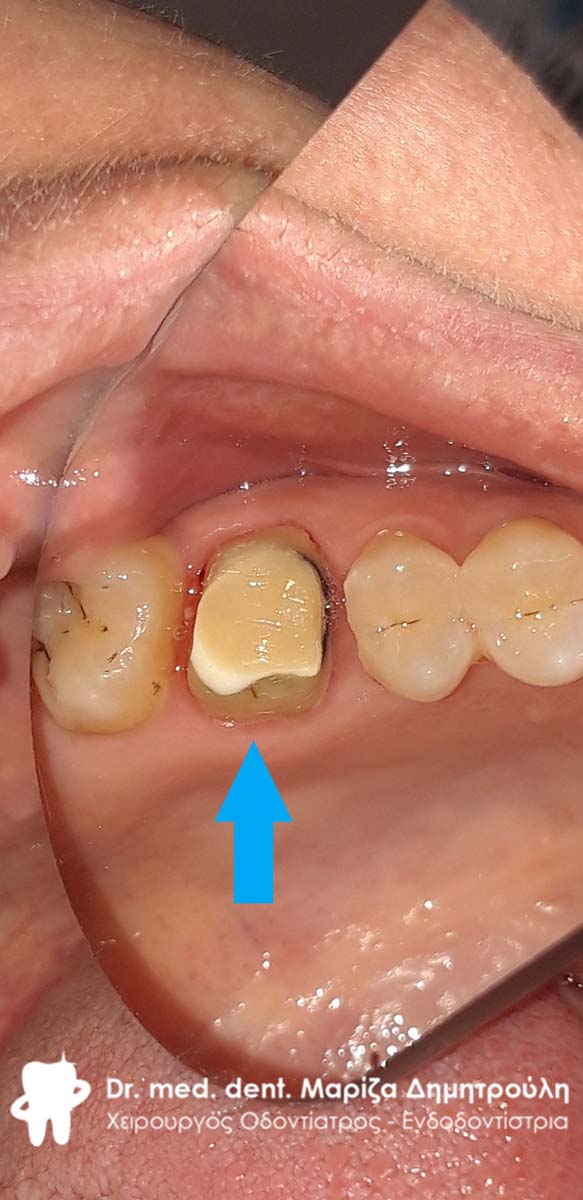

Αρχική κλινική εικόνα του μεγάλου οδοντικού ελλείμματος